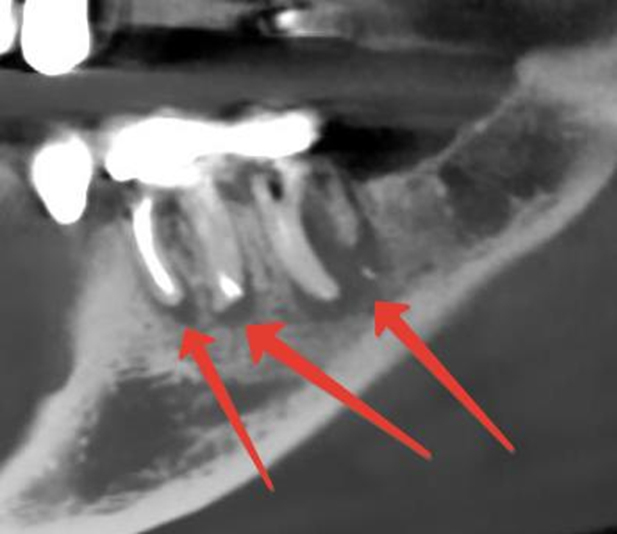

4 ) Лечение периодонтита (воспаление тканей окружающих корень зуба, или как вы любите «киста на корне») с применением эндодонтических инструментов и пломбировочных материалов отечественного производства

Аналогично — всё по стандартам, с отечественными расходниками, но это в теории. На практике лечение периодонтита в вышеуказанных условиях будет иметь прогноз даже хуже обычного.

При острых периодонтитах используют старую методику «открытого» зуба. Когда зуб тупо раскрывают, удаляют остатки нерва и назначают полоскание антисептиком, чтобы якобы был отток воспаления из корня.

Про то как правильно лечить острые периодонтиты напишу отдельно, но суть в том, что зуб ни в коем случае открытым оставлять нельзя, так как микрофлора полости рта устремляется в канал зуба и его потом хрен отмоешь.

Если периодонтит хронический (киста), то прогноз ещё хуже, так как зуб пропитан инфекцией ещё глубже. Лечение таких зубов априори идет без гарантии у любого нормального доктора. Риск того, что потратишь деньги, время и в итоге зуб пойдет под удаление не самый низкий. А если умножить на условия, в которых он будет лечиться…ну вы поняли.

Многие доктора, понимая низкую перспективность сего дела сразу отправляют на удаление.